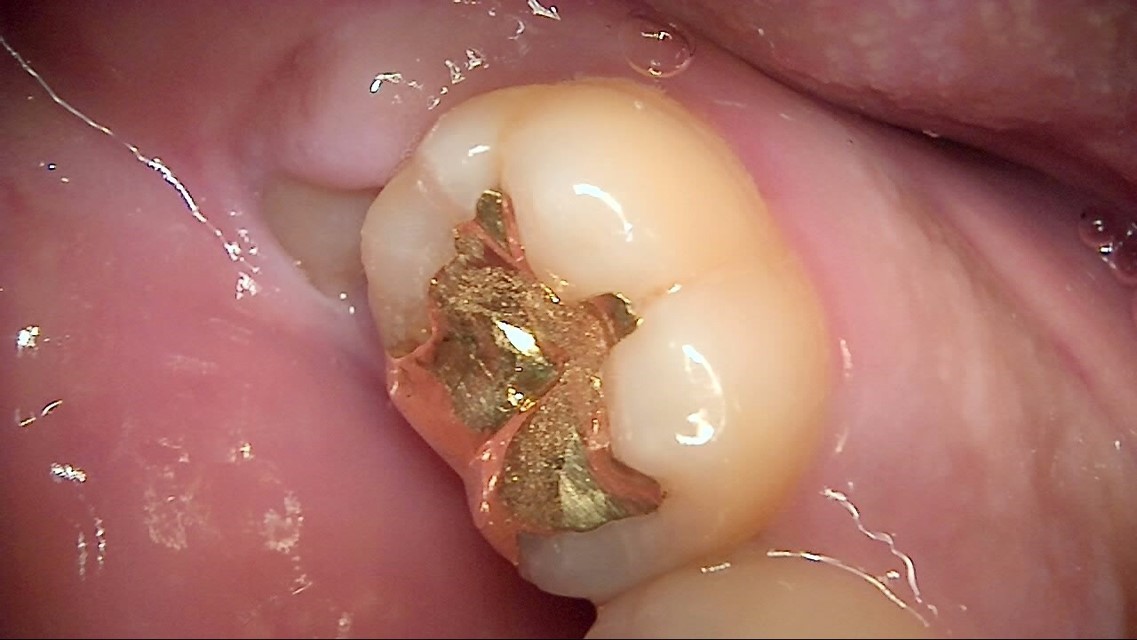

Crack

큐레이캠프로, 큐레이펜씨